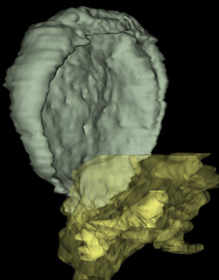

0 μm

Carnegie Embryo #7802 | Location: 43-02-04

Keywords: amniotic cavity, cephalic end of notochordal process, epiblast, extra-embryonic endoderm, hemangiogenic tissue, hypoblast, mesothelium of umbilical vesicle, presumptive neural plate, two-layered amnion, umbilical vesicle cavity

Source: The Virtual Human Embryo.